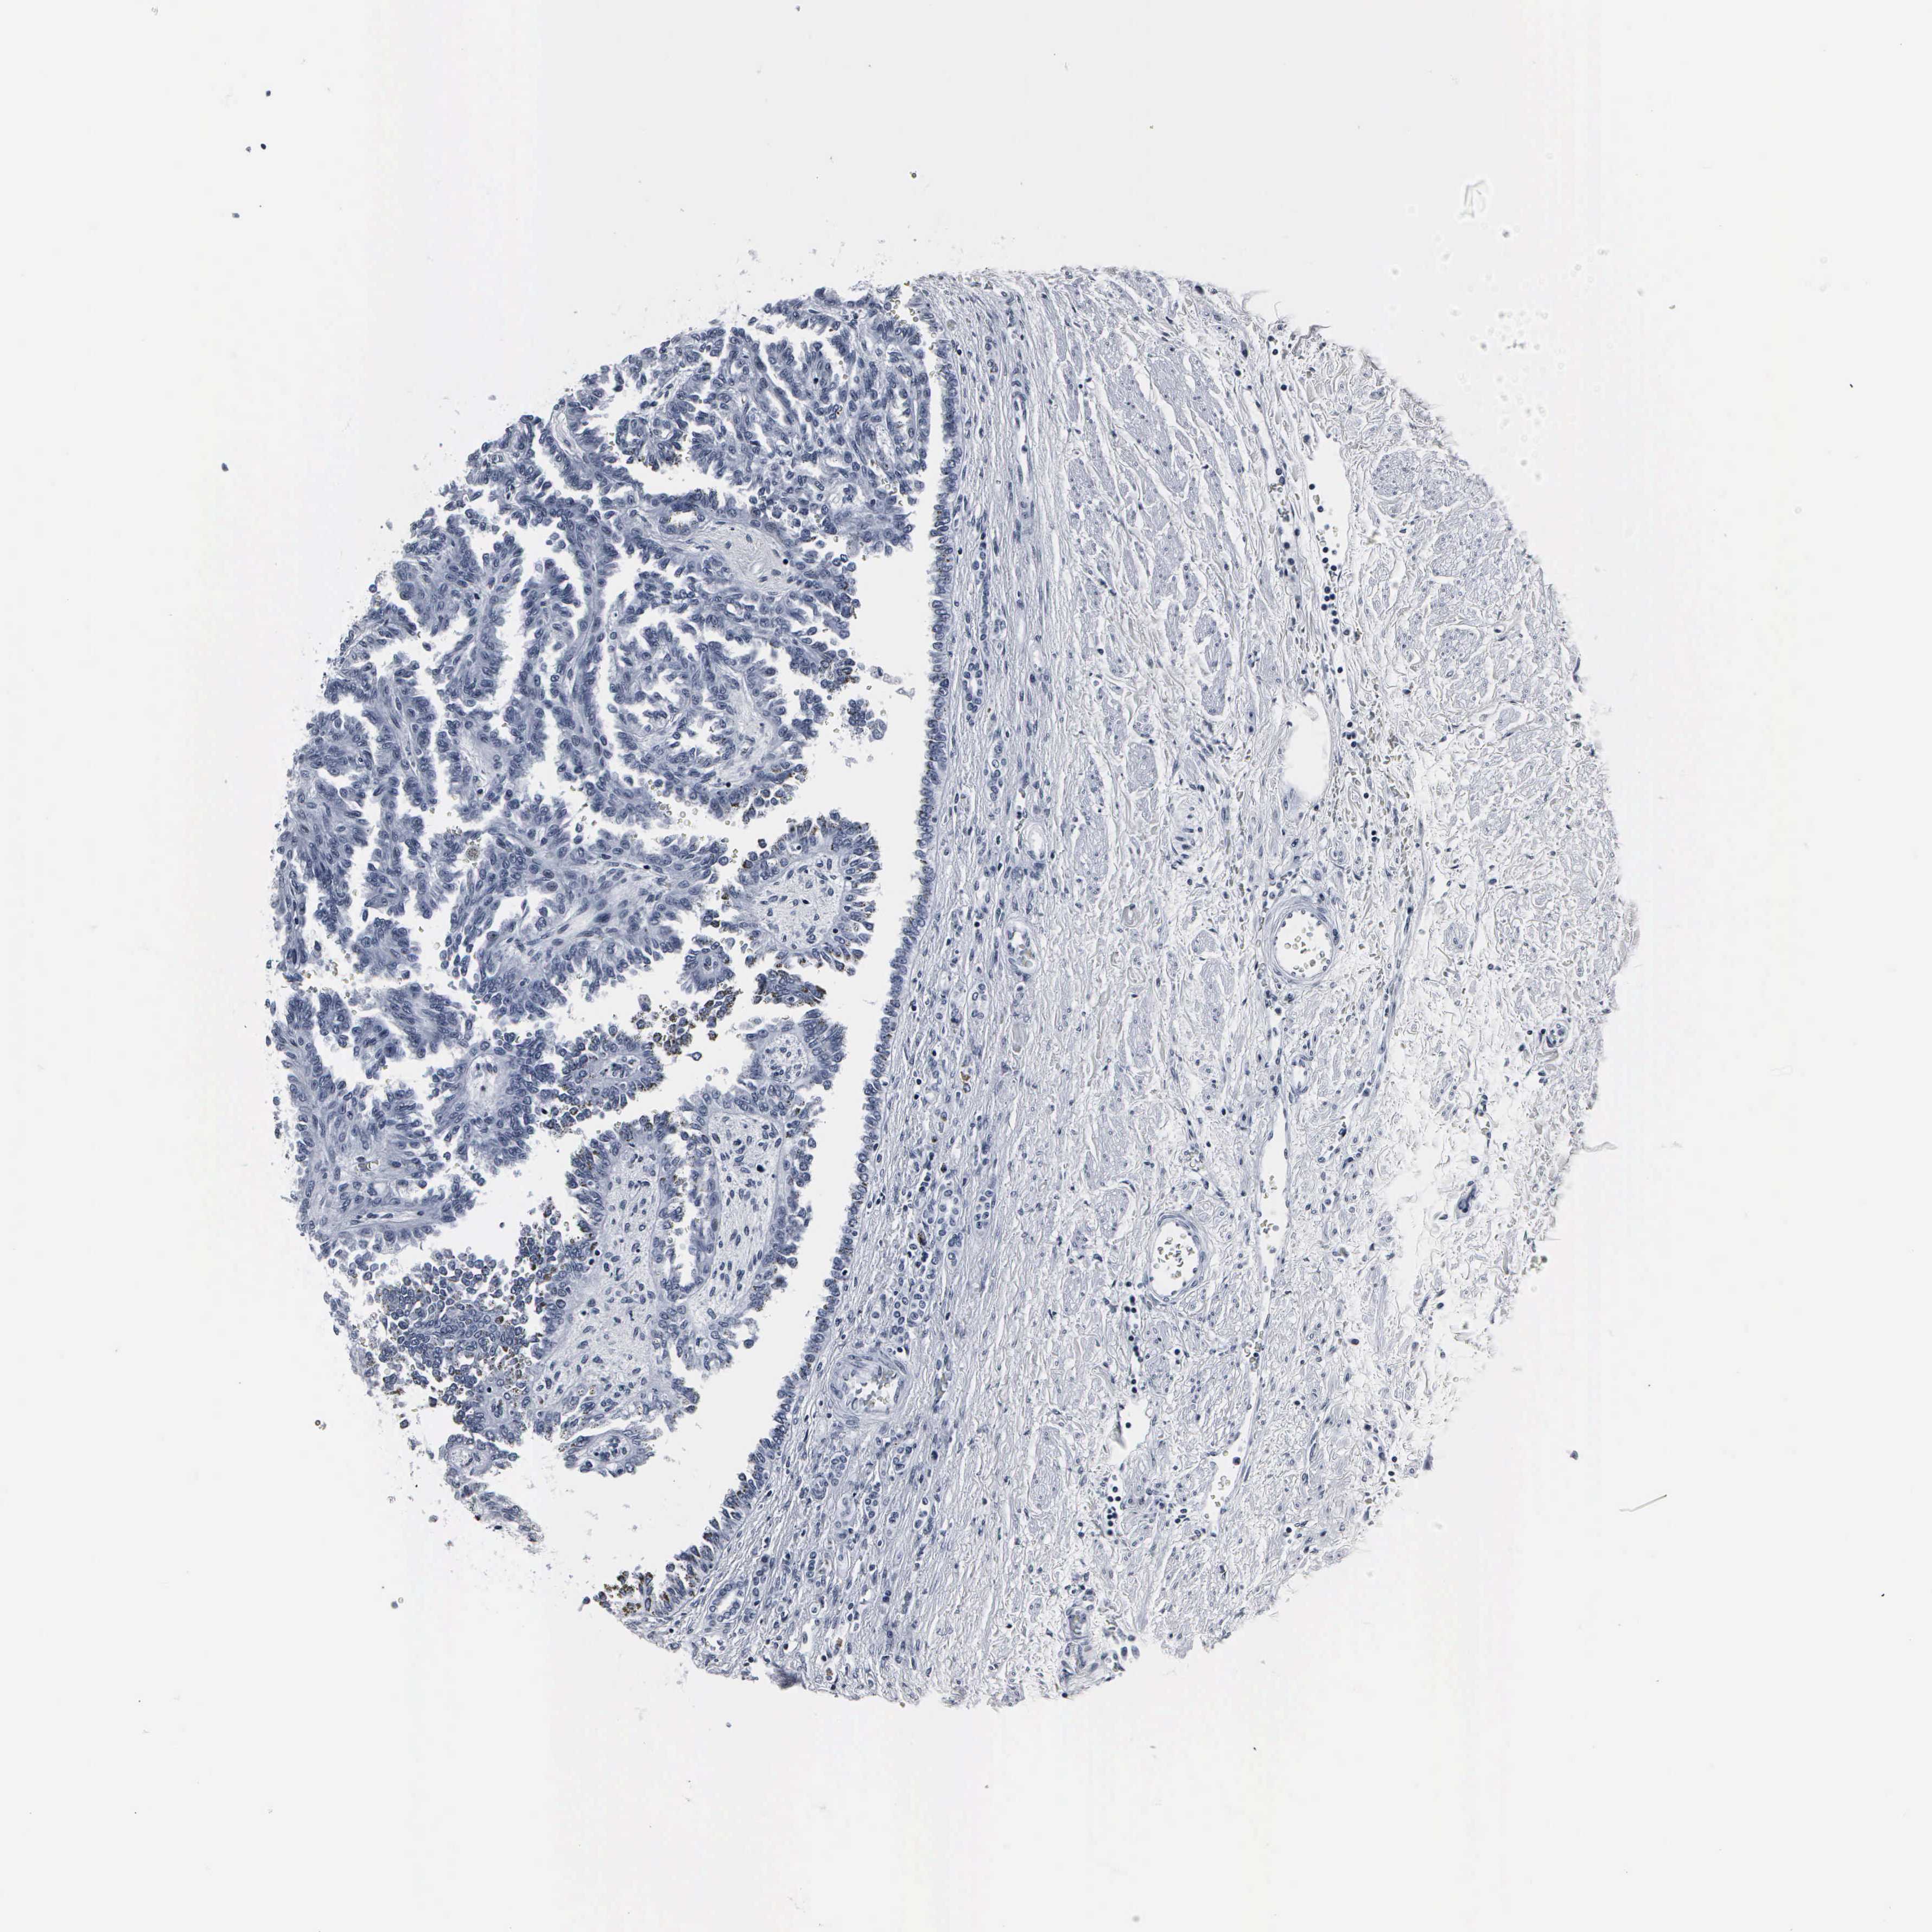

CANCER RENAL CANCER Show tissue menu

KICH TCGA KIRC TCGA KIRC VALIDATION KIRP TCGA PROTEIN RCC CPTAC PROTEIN EXPRESSION